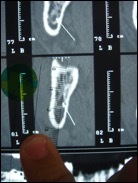

Il faut rechercher également les foyers infectieux et préciser la situation des sinus maxillaire et du nerf mandibulaire (qui traverse la mandibule) avant d’envisager la pose d’implants.

En cas d’obstacle anatomique (nerf trop proche, quantité d’os insuffisante…) une chirurgie pré-implantaire doit être programmée. Ainsi des greffes osseuses peuvent être envisagées avant la pose des implants, ou un déroutement des nerfs dentaires.